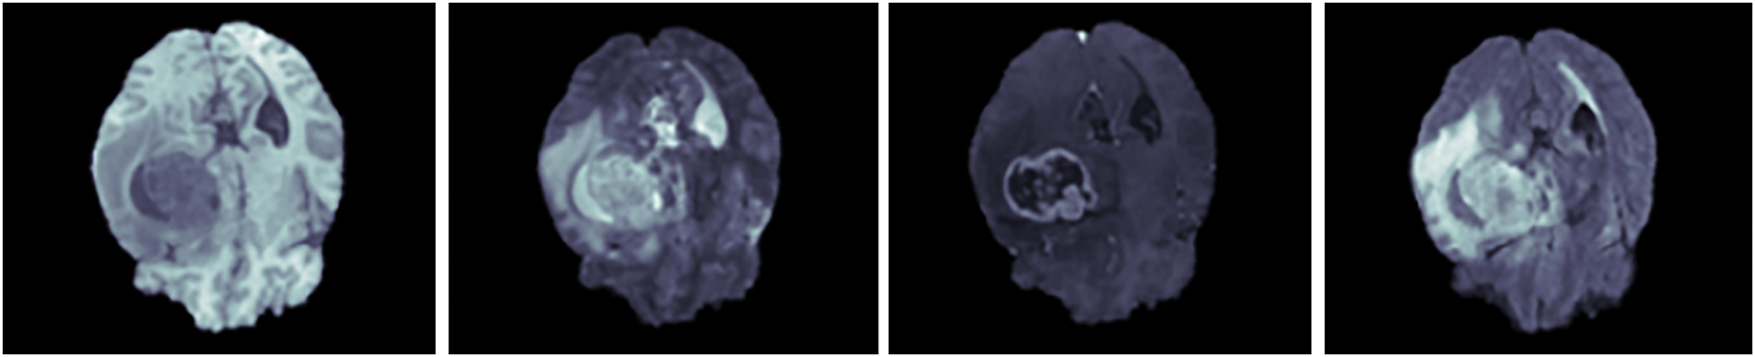

The Dataset 2 (BraTS 2019) is made of 76 lower and 259 higher-grade glioma images. The ground truth in this dataset is manually created using an annotation protocol carried out by neuro-radiologists [39]. The dataset contains MRI brain scans from four modalities: T2, T1, T2-FLAIR and T1-CE. The sample MRI brain scans of Dataset 2 are given in Fig. 2.

Figure 2: Sample MRI brain scans of Dataset 2

Additionally, Dataset 3 (BraTS 2020) comprises of 369 subject data with four modalities which are, Post Contrast T1 weighted (T1CE), T2 weighted (T2), native (T1), and T2 Fluid Attenuated Inversion Recovery (FLAIR) segmented manually, alongside 125 subject data segmented without manual intervention [40]. Furthermore, the sample MRI brain scans of Dataset 3 are illustrated in Fig. 3.

Figure 3: Sample MRI brain scans of Dataset 3